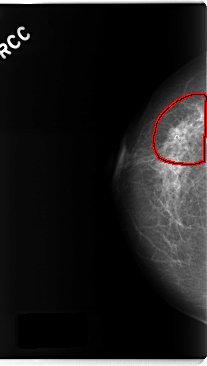

FILE: C_0186_1.RIGHT_CC.OVERLAY

TOTAL_ABNORMALITIES 1

ABNORMALITY 1

LESION_TYPE CALCIFICATION TYPE PLEOMORPHIC DISTRIBUTION SEGMENTAL

LESION_TYPE MASS SHAPE IRREGULAR MARGINS SPICULATED

ASSESSMENT 5

SUBTLETY 5

PATHOLOGY MALIGNANT

TOTAL_OUTLINES 1

BOUNDARY